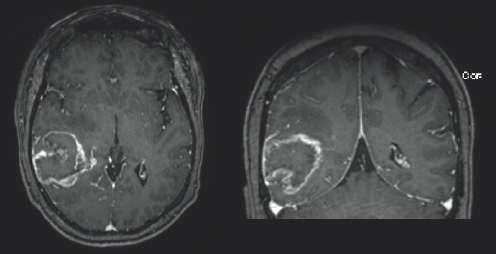

Light gray color variations are surrounded by black space and a white outline. On the top right of the image, near the midline, there is a white blob highlighted by a white circle. (Right) Charcoal gray color variations are surrounded by black space and a light gray outline.

FIGURE 3.4 Brain MRI after surgery. Follow-up axial (left) and coronal (right) post-contrast images, obtained 39 months follow-up, show progressive increased size of an abnormal ependymal enhancing nodule in the left frontal horn (white circle) that appears bright after being injected with IV contrast, consistent with a recurrent tumor.

A month after her surgery, Janet began chemotherapy and radiation treatment. She began trialing different chemotherapy drugs recommended by her team of physicians to pinpoint which would be most effective for her tumor. She was unable to be treated with the standard-of-care drug, TMZ, due to a severe anaphylactic allergic reaction. Despite desensitization to try to ween her on TMZ use, she continued treatment with lomustine, a different chemotherapy drug. Janet was placed on multiple clinical trials starting with the Belinostat/MRSI (magnetic resonance spectroscopic imaging) study and later the 5-ALA (5-aminolevulinic acid) study. Early on in her treatment, Janet turned to tumor treating fields (TTFs), to see if that form of treatment could provide her the benefit of tumor reduction. TTFs are commonly used in the form of an Optune® device. An Optune® device is a physical, white-colored cap that patients can place over their shaved heads to reduce cancer cell growth through the electric fields that the device omits. In the fall of 2019, Janet moved her care from Emory University Hospital and Wake Forest Hospital to the University of Cincinnati Medical Center to follow her neuro-oncologist, Dr. Soma Sengupta, with whom she had formed a close relationship. Due to the progression of her disease Janet underwent a re-resection surgery in March of 2020 and was placed on the adjuvant letrozole drug study. She then started the chemotherapy drug bevacizumab and required stereotactic radiosurgery (SRS) for a new lesion (Fig. 3.2–3.4). She continued care through her doctors in Cincinnati in conjunction with the care she was receiving at Wake Forest Hospital. She felt prepared but nervous each time she underwent imaging because she knew if her tumor had grown, it would result in a change of course to her treatment.